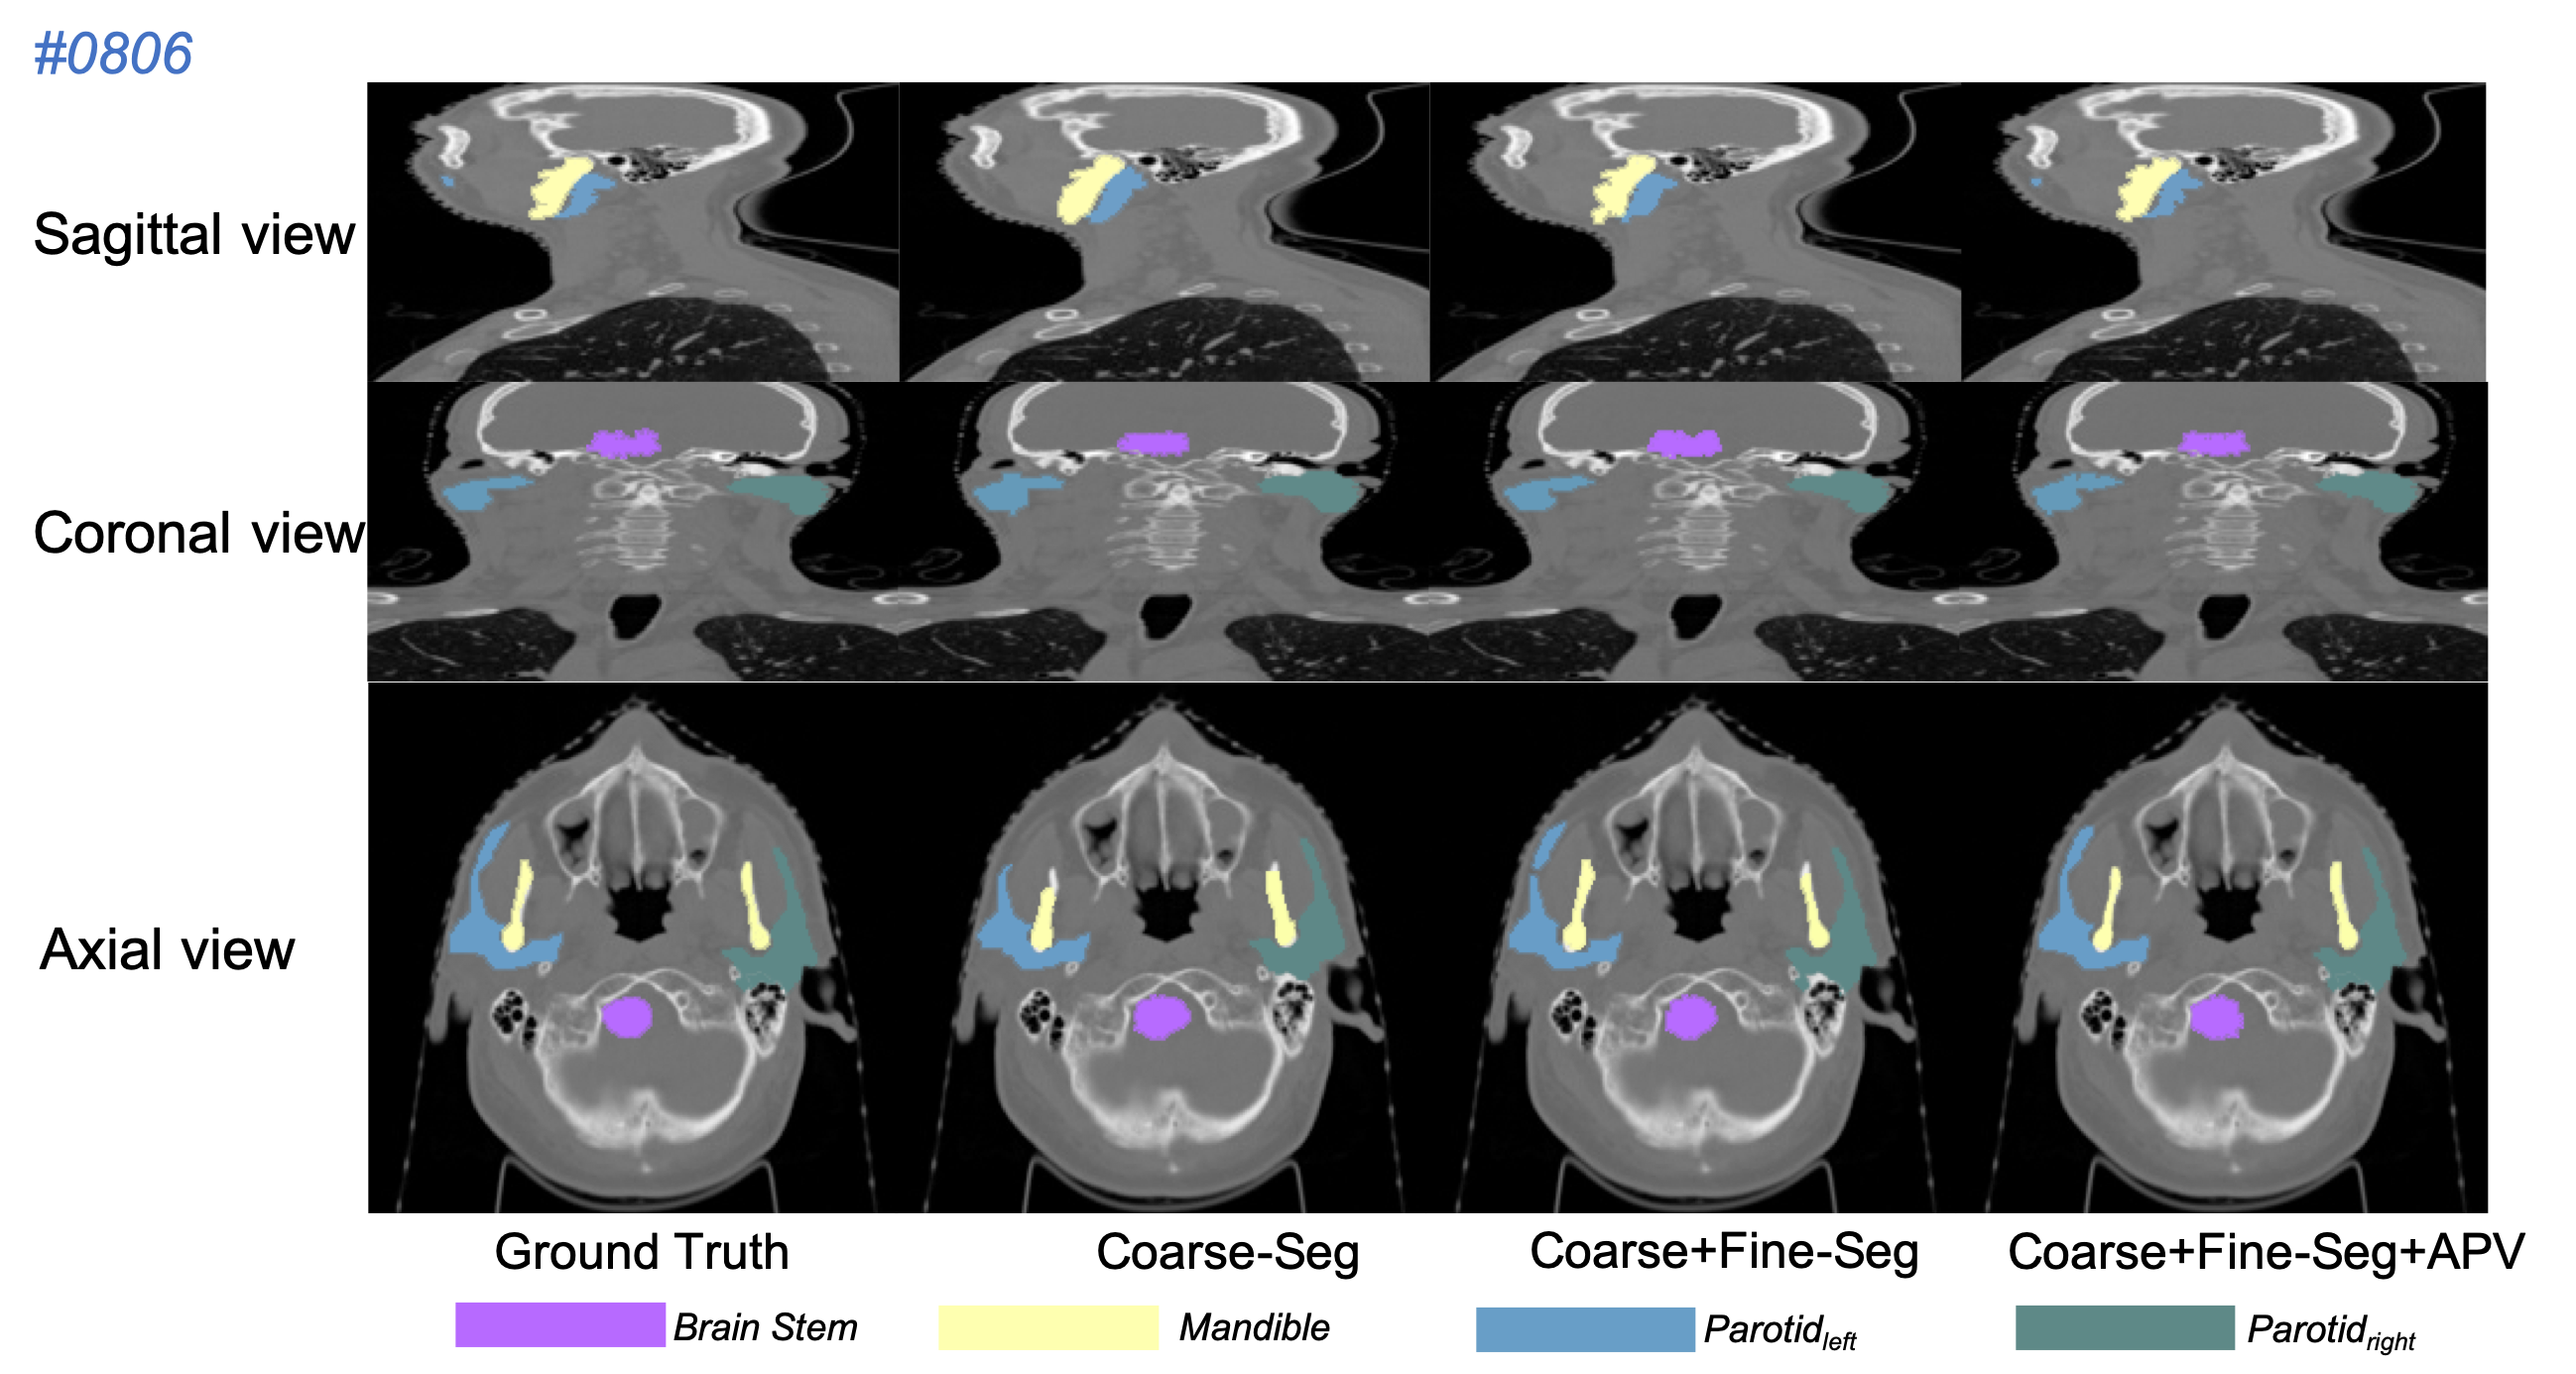

Refer to caption

Figure 5: Segmentation results of our proposed method on the PDDCA dataset.

The Quantitative comparison in Tab. 1 demonstrates that the proposed network outperforms several state-of-the-art architectures based on the average DSC (%) accuracy and is capable of segmenting organs from multi-classes robustly. Our coarse-to-Fine framework both without (Our-F) and with APV (Our-A) show competitive performance in direct comparison with the active appearance model method [19] and current learning-based approaches [13, 40]. Although [40] shares similar coarse-to-fine architecture but processes only on 2D slices in fine-scale segmentation, our based-model (Our-F) directly exploits 3D volumes and learns structural information so as to achieve a higher accuracy. Enhanced by APV module, the refined segmentation (Our-A) gets highest DSC accuracy among all reported methods. Test results on patient samples randomly selected from the PDDCA validation dataset (Fig. 5) visually illustrate that the proposed method gives three-level segmentation: (1) the coarse-scale segmentation (Fig. 5 Coarse-seg) predict a rough location and shape of the OARs; (2) the fine-scale segmentation (Fig. 5 Coarse+Fine-seg) estimates a detail boundary of each OARs but still with some flaws; (3) the APV-refined segmentation (Fig. 5 Coarse+Fine+APV-seg) generates 3D mask which is able to overlap the OARs perfectly.